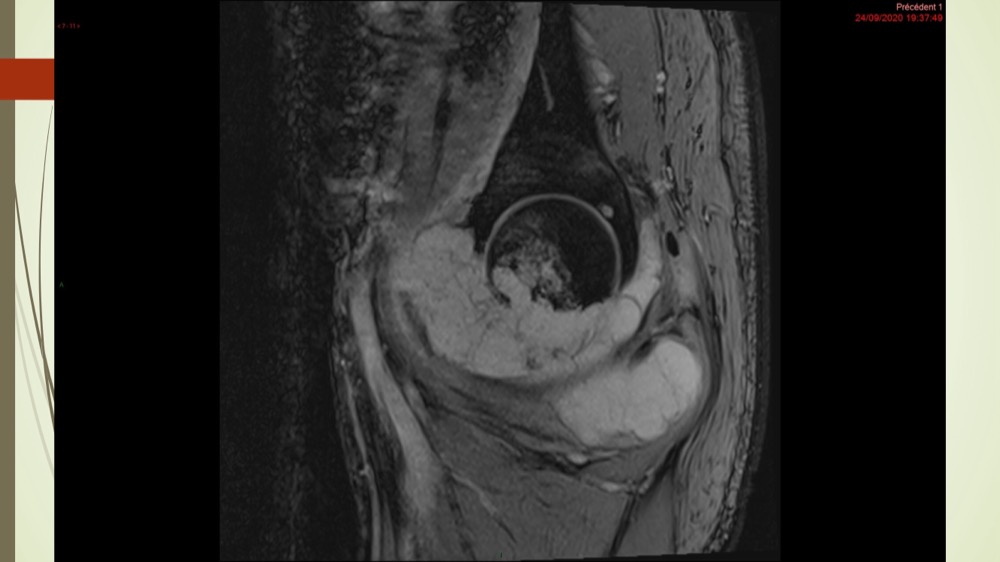

Coxalgie traînante

Kévin Mahé 29/06/2022